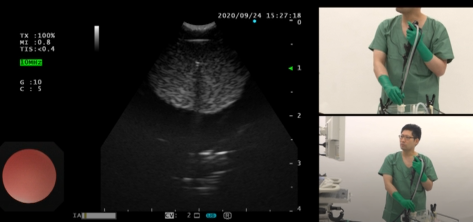

本ビデオレクチャーでは右肺の下葉に原発巣があることを想定し、リンパ節のステージングをモデルを用いて実施します。

大事な点として、ステージングでは内腔画面でどの位置にいるかを確認しながら、リンパ節番号を間違えず観察していくことにあります。

ステージングの場合、穿刺は転移可能性が低いもの、同程度であれば、遠い位置から刺していくことも重要です。穿刺・吸引の手順とコツ、加えて検体処理方法も紹介していきます。